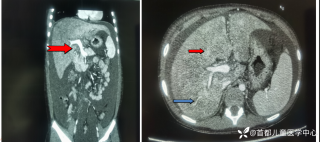

灼见|如果是你,如何处置山东男孩(多器官切除病例)

文/西地兰 特别声明:所有观点仅代表个人言论 特别声明:与当事双方均无利益相关 山东男孩,目前全网沸沸扬扬,看过一些观点,直言不讳地说,大多偏颇。要么一股脑地指责医方的全责,甚至有说千万别在县医院看病。要么又为医方无休止的遮羞,认为这样的手术在县医院做下来已经非常了不起。而我想到的是,以后面临类似的病例,我们怎么办?那么我们不如来一次专业的病案讨论。既然是事后讨论,难免有事后诸葛亮的感觉,但是假如下一次,同行们遭遇这样的病例,如何处置?这是医疗行业所面临的问题。希望我整理的这些思路和相关病例,对同行们有所帮助!就目前的资讯外界不足以判断是否需要急诊,如果需要急诊,那么只能根据术中所见进行处理,

目前知道的消息,第一,术前发现一个血肿,然后做增强CT发现一个占位,没说血肿与肿瘤的关系,术后病理没有描述肿瘤出现破裂出血,大概率就一个小血肿,我就不明白当地主任凭哪个指针去给这小孩开急诊刀的?哪个指南告诉他需要急诊开?第二,诊断不明确他想的不是进一步检查,一边观察一边进一步查,他反而选择腹腔镜探查,这个探查的指针在哪?第三,腹腔一个血肿,没有活动性出血,没有血压心率出现问题,为什么要开腹进去碰它?不能等血肿吸收再明确肿瘤性质吗?第四,1点进腹,3点病理结果出来,按这个时间还算顺利,应该还没出事,孩子还算平稳,病理是低度恶性,切了就治愈,他一年能开几台这手术,就敢继续做,拿孩子练手。第五,后面

2023年10月26日,来自山东菏泽市成武县的小烨和他家人的命运被彻底改变了。这个原本阳光、可爱的小男孩在一次意外被撞击后,在医院检查出了腹腔内存在肿瘤,并在手术中被切除了包括十二指肠、胰腺、大部分胃和小肠等多个器官。此后便无法再像正常人一样吃饭、喝水,活着要靠长期静脉注射营养液。一份2024年12月由第三方机构出具的司法鉴定意见书显示,当时给小烨做手术的成武县人民医院在该医疗行为中存在过错,与小烨的损害后果之间存在因果关系,建议医疗过错在损害后果中的原因力大小为同等原因。此外,另一份由成武县卫生健康局在2025年9月28日发出的书面答复中显示,成武县人民医院存在24小时内未完成病历;手术知情